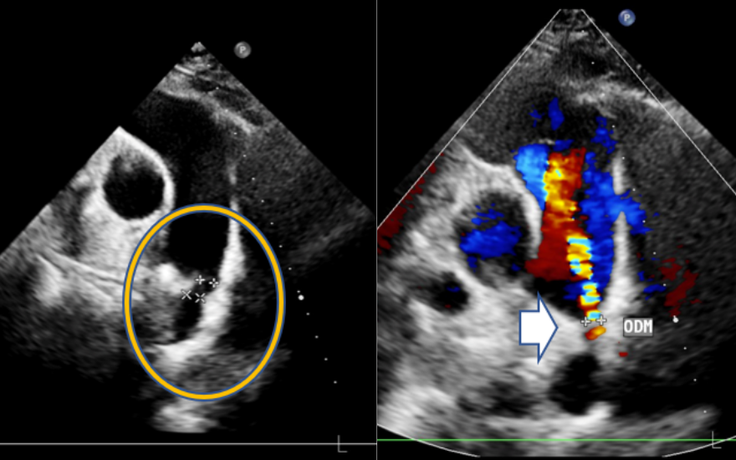

Rút ngắn thời gian nằm viện sau can thiệp tim mạch: Yếu tố nào quyết định?

Trước đây, nhiều bệnh nhân tim mạch, đặc biệt là người cao tuổi phải nằm viện khoảng một tuần sau can thiệp. Tuy nhiên hiện nay, nhờ điều trị đúng thời điểm cùng quy trình chăm sóc bài bản, không ít người bệnh có thể phục hồi nhanh hơn và xuất viện chỉ sau 2-3 ngày.

Bàng hoàng phát hiện dị tật tim bẩm sinh sau hơn 30 năm sống khỏe mạnh